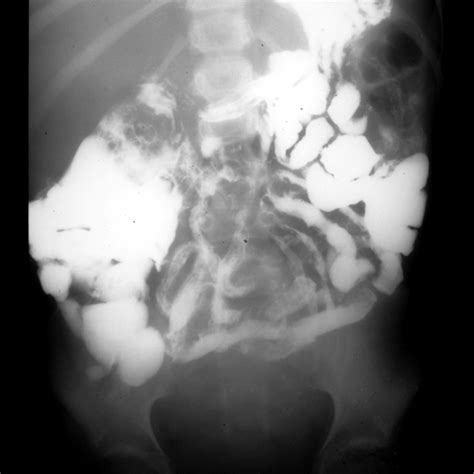

A Small Bowel Follow Through (SBFT) is a fluoroscopic examination—essentially a "moving X-ray"—that tracks the movement of a contrast material, typically barium, through the small intestine. While a standard abdominal X-ray can show gas patterns or obstructions, it cannot visualize the delicate lining of the small bowel. By drinking a contrast agent that is opaque to X-rays, the anatomy of your digestive tract becomes highlighted on the screen, allowing radiologists to identify structural abnormalities, blockages, or signs of inflammation.

This diagnostic test is particularly useful for identifying conditions that affect the length and texture of the small bowel. It is often requested when a patient presents with symptoms such as diarrhea, blood in the stool, or suspected malabsorption disorders. Unlike a capsule endoscopy, which uses a tiny camera, the SBFT provides a functional view, showing how quickly the digestive contents pass through the system (motility).